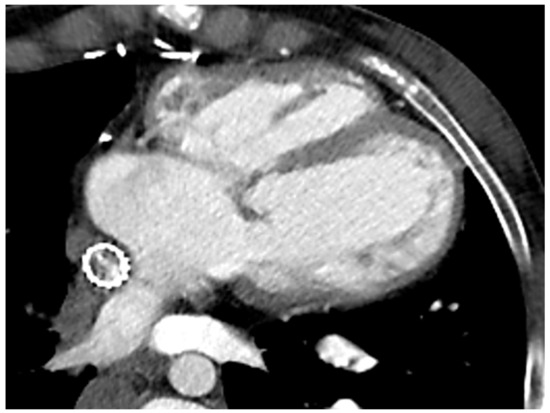

Due to ionizing radiation exposure, CCT has been historically overlooked in CHD patients, particularly in those requiring serial imaging evaluation. However, the introduction of new generation scanners and the new strategies adopted to minimise both radiation exposure and acquisition time have significantly increased the role of CCT even in this clinical scenario. The use of dual-source or wide-detector scanners, as well as sucrose oral administration and immobilisation devices in neonates, allows for obtaining good quality images even in the youngest of patients, without the need for sedation or general anaesthesia [46]. The latter should be reserved for extremely non-compliant patients or if longer acquisition times are expected due to the use of older scanners. The risk of serious adverse events is low but not negligible, thus requiring adequately trained staff and appropriate equipment [47]. In order to reduce radiation exposure, a scan should be limited to the region of interest, positioning the heart at the isocenter of the gantry and using the appropriate tube potential and tube current [46]. All these precautions seem sufficient to minimise exposure, so organ shielding is not routinely recommended in the paediatric population due to the potential risk of interference with automated dose-modulation systems [48]. To further reduce the radiation dose, a non-contrast scan should be avoided due to the very limited information provided in this clinical context. Conversely, iodinate contrast is crucial, and the administration protocol should be tailored to answer the clinical question with the smallest amount of contrast, avoiding unnecessary repeated acquisition. The aim would be to acquire the images when the contrast has an optimal concentration in the region of interest, by using faster acquisition protocols and considering the cardiac output, the site of injection, and the injection rate. Particular attention should be paid to eliminating all the air bubbles from the contrast, particularly in these patients, due to the presence of septal defects, fenestration, and collaterals and the consequent potential risk of right-to-left embolization (Figure 4).

In patients with a Fontan anatomy, CT could be the preferred imaging modality when a concomitant evaluation of the coronary anatomy is required or in the presence of cardiac devices (either contraindicated or the source of unpredictable artefacts in CMR) [32,33,34]. This may be particularly relevant when considering the increased risk of pacemaker implantation described in this population [49]. An ECG-gated CT can also accurately provide information about left-ventricular volumes and function with good agreement with CMR measurements, despite the lower temporal resolution [50]. However, this requires a higher dose of radiation and an optimised contrast-acquisition protocol if right-chamber quantification is also needed, to maximise RV opacification and minimise artefacts [50]. The major indication in Fontan patients for CCT remains the evaluation of potential thromboembolic complications, occurring in 1–33% of patients and still representing one of the major causes of morbidity and mortality [51]. Thrombi usually appear as hypodense eccentric areas within a vessel after contrast administration that persist in the delayed phase. Obtaining a homogenous opacification of the pulmonary vessels could be particularly challenging in Fontan patients due to the peculiar anatomy and the consequent different timing of contrast arrival in the left and right systems. This generates a mixture of opacified and non-opacified blood that could generate artefacts and mimic the presence of a thrombus [52]. To avoid this possible pitfall, different protocols have been proposed, such as changing the number of sites of injection or the number and timing of the acquisition phases [53]. In the dual-injection protocol, two veins (from the upper and lower venous systems) are cannulated and used for simultaneous contrast injection. Despite increasing the diagnostic performance, this technique has the obvious limitations of double venous access, which is sometimes difficult to obtain, and the discomfort related to the multiple contrast injections. Single-injection protocols with either a single-but-delayed phase at 75–80 s or a dual-phase acquisition have also been proposed, which demonstrated a greater accuracy when compared to traditional protocols [53]. CCT is also useful in detecting and quantifying stenosis of the conduit due to calcification or intimal hyperplasia and could be used for pre-procedural assessment [54]. Due to its excellent spatial resolution, CCT can also accurately visualise aortopulmonary collaterals, pulmonary arteriovenous malformations, or systemic-to-pulmonary venous collaterals that guide the percutaneous procedures or evaluate the outcomes during follow-up [55]. Fontan patients often suffer from liver disease, a consequence of the chronic, systemic venous hypertension. An abdominal CT early identifies hepatic congestion as a reticular enhancement in the portal venous phase. Focal nodular hyperplasia-like (FNH-like) lesions are also a common finding in Fontan patients. These appear as hyso-hypodense lesions, quickly enhancing in the arterial phase and becoming hypo-hysodense in the portal venous and delayed phases, with possible residual enhancement of the central scar [56]. Hepatocellular carcinoma shares some common imaging features with FNH-like lesions, but the atypical enhancement patterns could represent a red flag for a differential diagnosis [57]. Cardiac CT is, therefore, a valuable alternative to other imaging modalities for biventricular volumes and function evaluation, particularly when dealing with patients with a poor acoustic window, patients unable to lie flat for long time, or patients with cardiac devices. CCT could be recommended for pre-operative assessment, with the possibility of obtaining 3D models that are helpful in surgical planning and training. In addition, CT angiography is the key modality for the evaluation of thromboembolic complications and is helpful in evaluating stent patency as well as patency of the pathway and the presence of collaterals. Beyond cardiovascular examination, CT could be also required for lung evaluation in the case of suspected plastic bronchitis or to assess the degree of hepatic involvement.

Figure 4. Cardiac CT in Fontan patient with stenting of the extracardiac conduit.